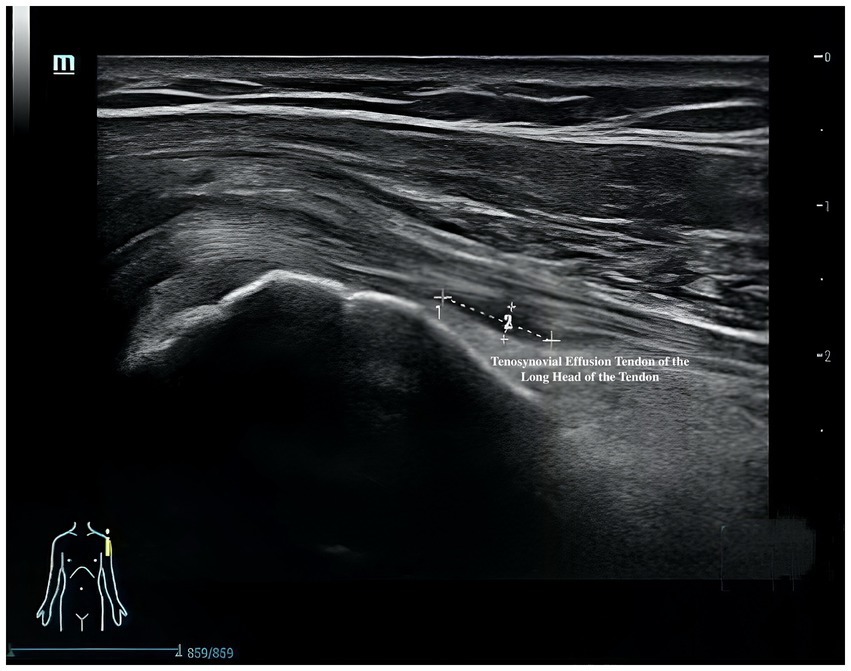

Musculoskeletal ultrasound is a practical and noninvasive method for detecting structural abnormalities commonly associated with PSSP. Key indicators include the distance from the acromion to the greater tuberosity of the humerus (Figure 9), effusion around the long head of the biceps tendon sheath (Figure 10), calcification in the supraspinatus (Figure 11) and subscapularis tendons, and increased thickness of the subdeltoid bursa (Figure 12). Effusion around the biceps tendon sheath often reflects inflammation or tendinopathy, which can contribute to pain and limited mobility. Calcifications in the supraspinatus and subscapularis tendons are typically associated with chronic rotator cuff conditions that result in impingement and reduced range of motion. Thickening of the subdeltoid bursa is suggestive of bursitis, a frequent source of discomfort in PSSP patients (21).

Figure 10

Ultrasound image showing a cross-sectional view of a tendon. It indicates the tenosynovial effusion in the tendon of the long head. A diagram of a human figure highlights the shoulder area.

Figure 10. Effusion around the long head of the biceps tendon sheath.